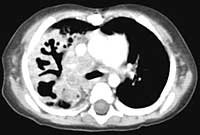

Below are CHEST CT results.

Enlarge

WHAT

IS YOUR INTERPRETATION FOR THE CHEST CT?